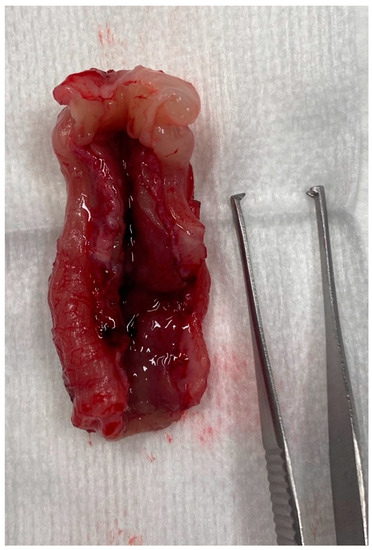

3.2.5. Histology

| Group A (9 Cases) | Group B (11 Cases) | |||

|---|---|---|---|---|

| Histological Findings | Number | Percentage (/20 Endoscopies) | Number | Percentage (/20 Endoscopies) |

| Mild-to-moderate LP infiltration | 6 | 30% | 10 | 50% |

| Marked LP infiltration | 2 | 10% | 1 | 5% |

| Neutrophilic infiltration | 5 | 25% | 4 | 20% |

| Fibrosis | 4 | 20% | 2 | 10% |

| Eosinophilic infiltration | 0 | 0% | 2 | 10% |

| Erosion/ulcers | 3 | 15% | 3 | 15% |